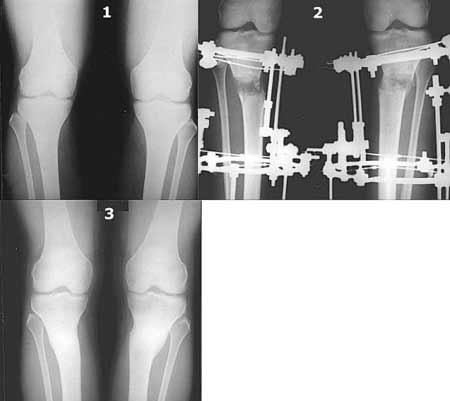

Вот ещё картинки, которые отправлял в Ортопод. Коррекция кривизны и удлинение на 3 см.